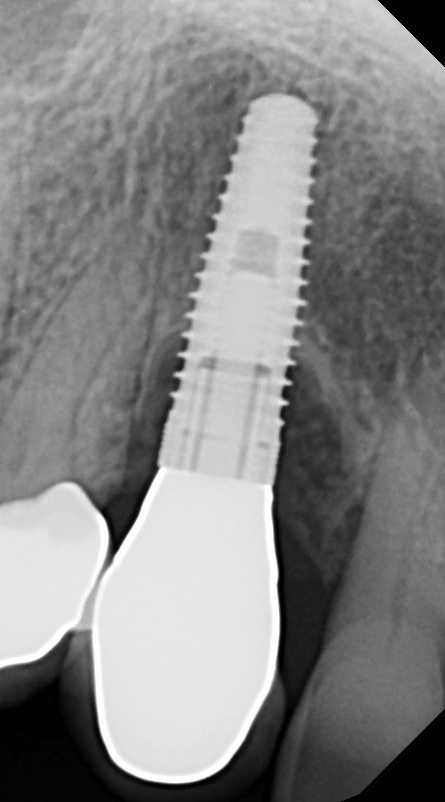

Fig 5. Radiograph 6 years after peri-implantitis repair (2014).

Figure 5